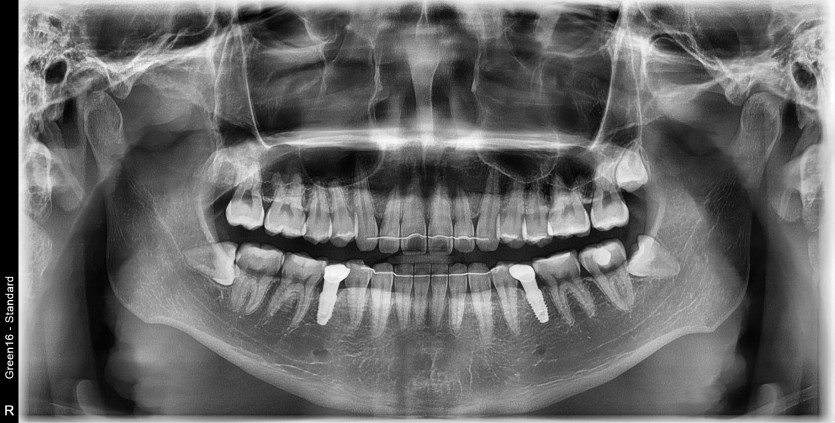

#18,28,38,48 사랑니 발치

구강 외과 전문의가 당일 발치했습니다.